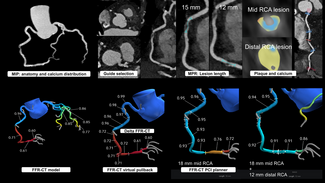

Coronary and graft angiography was performed via left transradial approach. Native coronary angiography revealed left coronary dominance with significant obstruction of the left main coronary artery by a single discrete lesion. The LAD and circumflex arteries were patent but diseased, with the occluded first obtuse marginal branch being supplied by a patent saphenous vein graft. Notably, competitive flow was present in the mid-LAD due to filling from both the proximal native vessel and LIMA graft (Figure 1, Video 1).

Coronary and graft angiography was performed via left transradial approach. Native coronary angiography revealed left coronary dominance with significant obstruction of the left main coronary artery by a single discrete lesion. The LAD and circumflex arteries were patent but diseased, with the occluded first obtuse marginal branch being supplied by a patent saphenous vein graft. Notably, competitive flow was present in the mid-LAD due to filling from both the proximal native vessel and LIMA graft (Figure 1, Video 1).

Based upon competitive flow noted during native vessel angiography, internal mammary graft patency was expected. Surprisingly, the LIMA was found to be proximally occluded (Figure 2). To reconcile the apparent discrepancy, exploration was performed for alternate sources of LAD filling. It was found that the LIMA downstream of the occluded origin filled via a single branch arising directly from the ipsilateral thyrocervical trunk (Figure 3, Video 2). The etiology of the proximal LIMA occlusion remains uncertain, but conceivably could have been related to vessel injury during coronary artery surgery. Regardless, an initial conservative strategy was felt appropriate, with the possibility of percutaneous intervention (native vessel or graft), or repeat CABG in the future, if required.

Based upon competitive flow noted during native vessel angiography, internal mammary graft patency was expected. Surprisingly, the LIMA was found to be proximally occluded (Figure 2). To reconcile the apparent discrepancy, exploration was performed for alternate sources of LAD filling. It was found that the LIMA downstream of the occluded origin filled via a single branch arising directly from the ipsilateral thyrocervical trunk (Figure 3, Video 2). The etiology of the proximal LIMA occlusion remains uncertain, but conceivably could have been related to vessel injury during coronary artery surgery. Regardless, an initial conservative strategy was felt appropriate, with the possibility of percutaneous intervention (native vessel or graft), or repeat CABG in the future, if required.